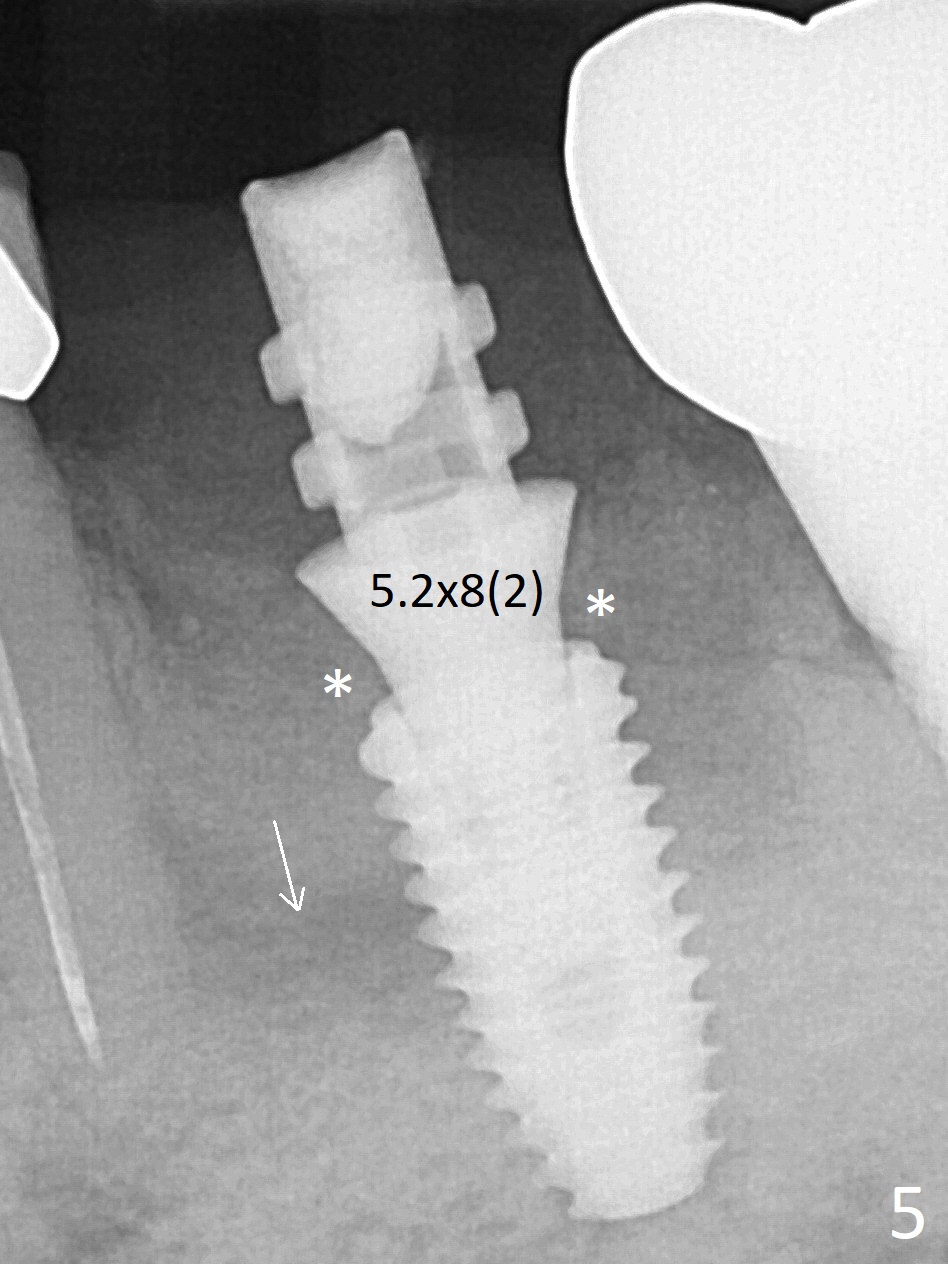

Extraction of the residual roots at #19 (Fig.1) is difficult, partially due to the hard one. The latter contributes to primary stability of 5x10 mm IS implant placed in the septum (Fig.2 (*),3). After change of cementation abutment (5.2x4.5(2) mm (short for provisional)) to hexed temporary abutment (5.2x8(2) mm), Collagen plug and Vera Graft are placed in the remaining mesial and distal socket (Fig.4 *). The last PA is taken when the temporary abutment (Fig.6 (<: hexed portion)) and provisional (P) are removed for modification. Before the abutment/provisional complex returns, a 2nd round of graft is placed (Fig.5 *). After the complex is seated, a 3rd round of graft is placed buccally (Fig.7). The temporary abutment is retightened 2 months postop (Fig.8). The implant appears to be osteointegrated 3.5 months postop (Fig.9). The gingiva looks healthy with (Fig.10) and without the provisional (Fig.11,12). It appears that there is no or minimal buccal plate loss. After insertion of a 5.7 x3 mm 15 degree (B-type) angled abutment (Fig.13) and height adjustment, impression is taken. The provisional is reseated after impression. The mesial bony defect seems to have been repaired nearly 8 months postop, 3 months post cementation (Fig.14 *). The bone density increases mesially 11 months post cementation (Fig.15).